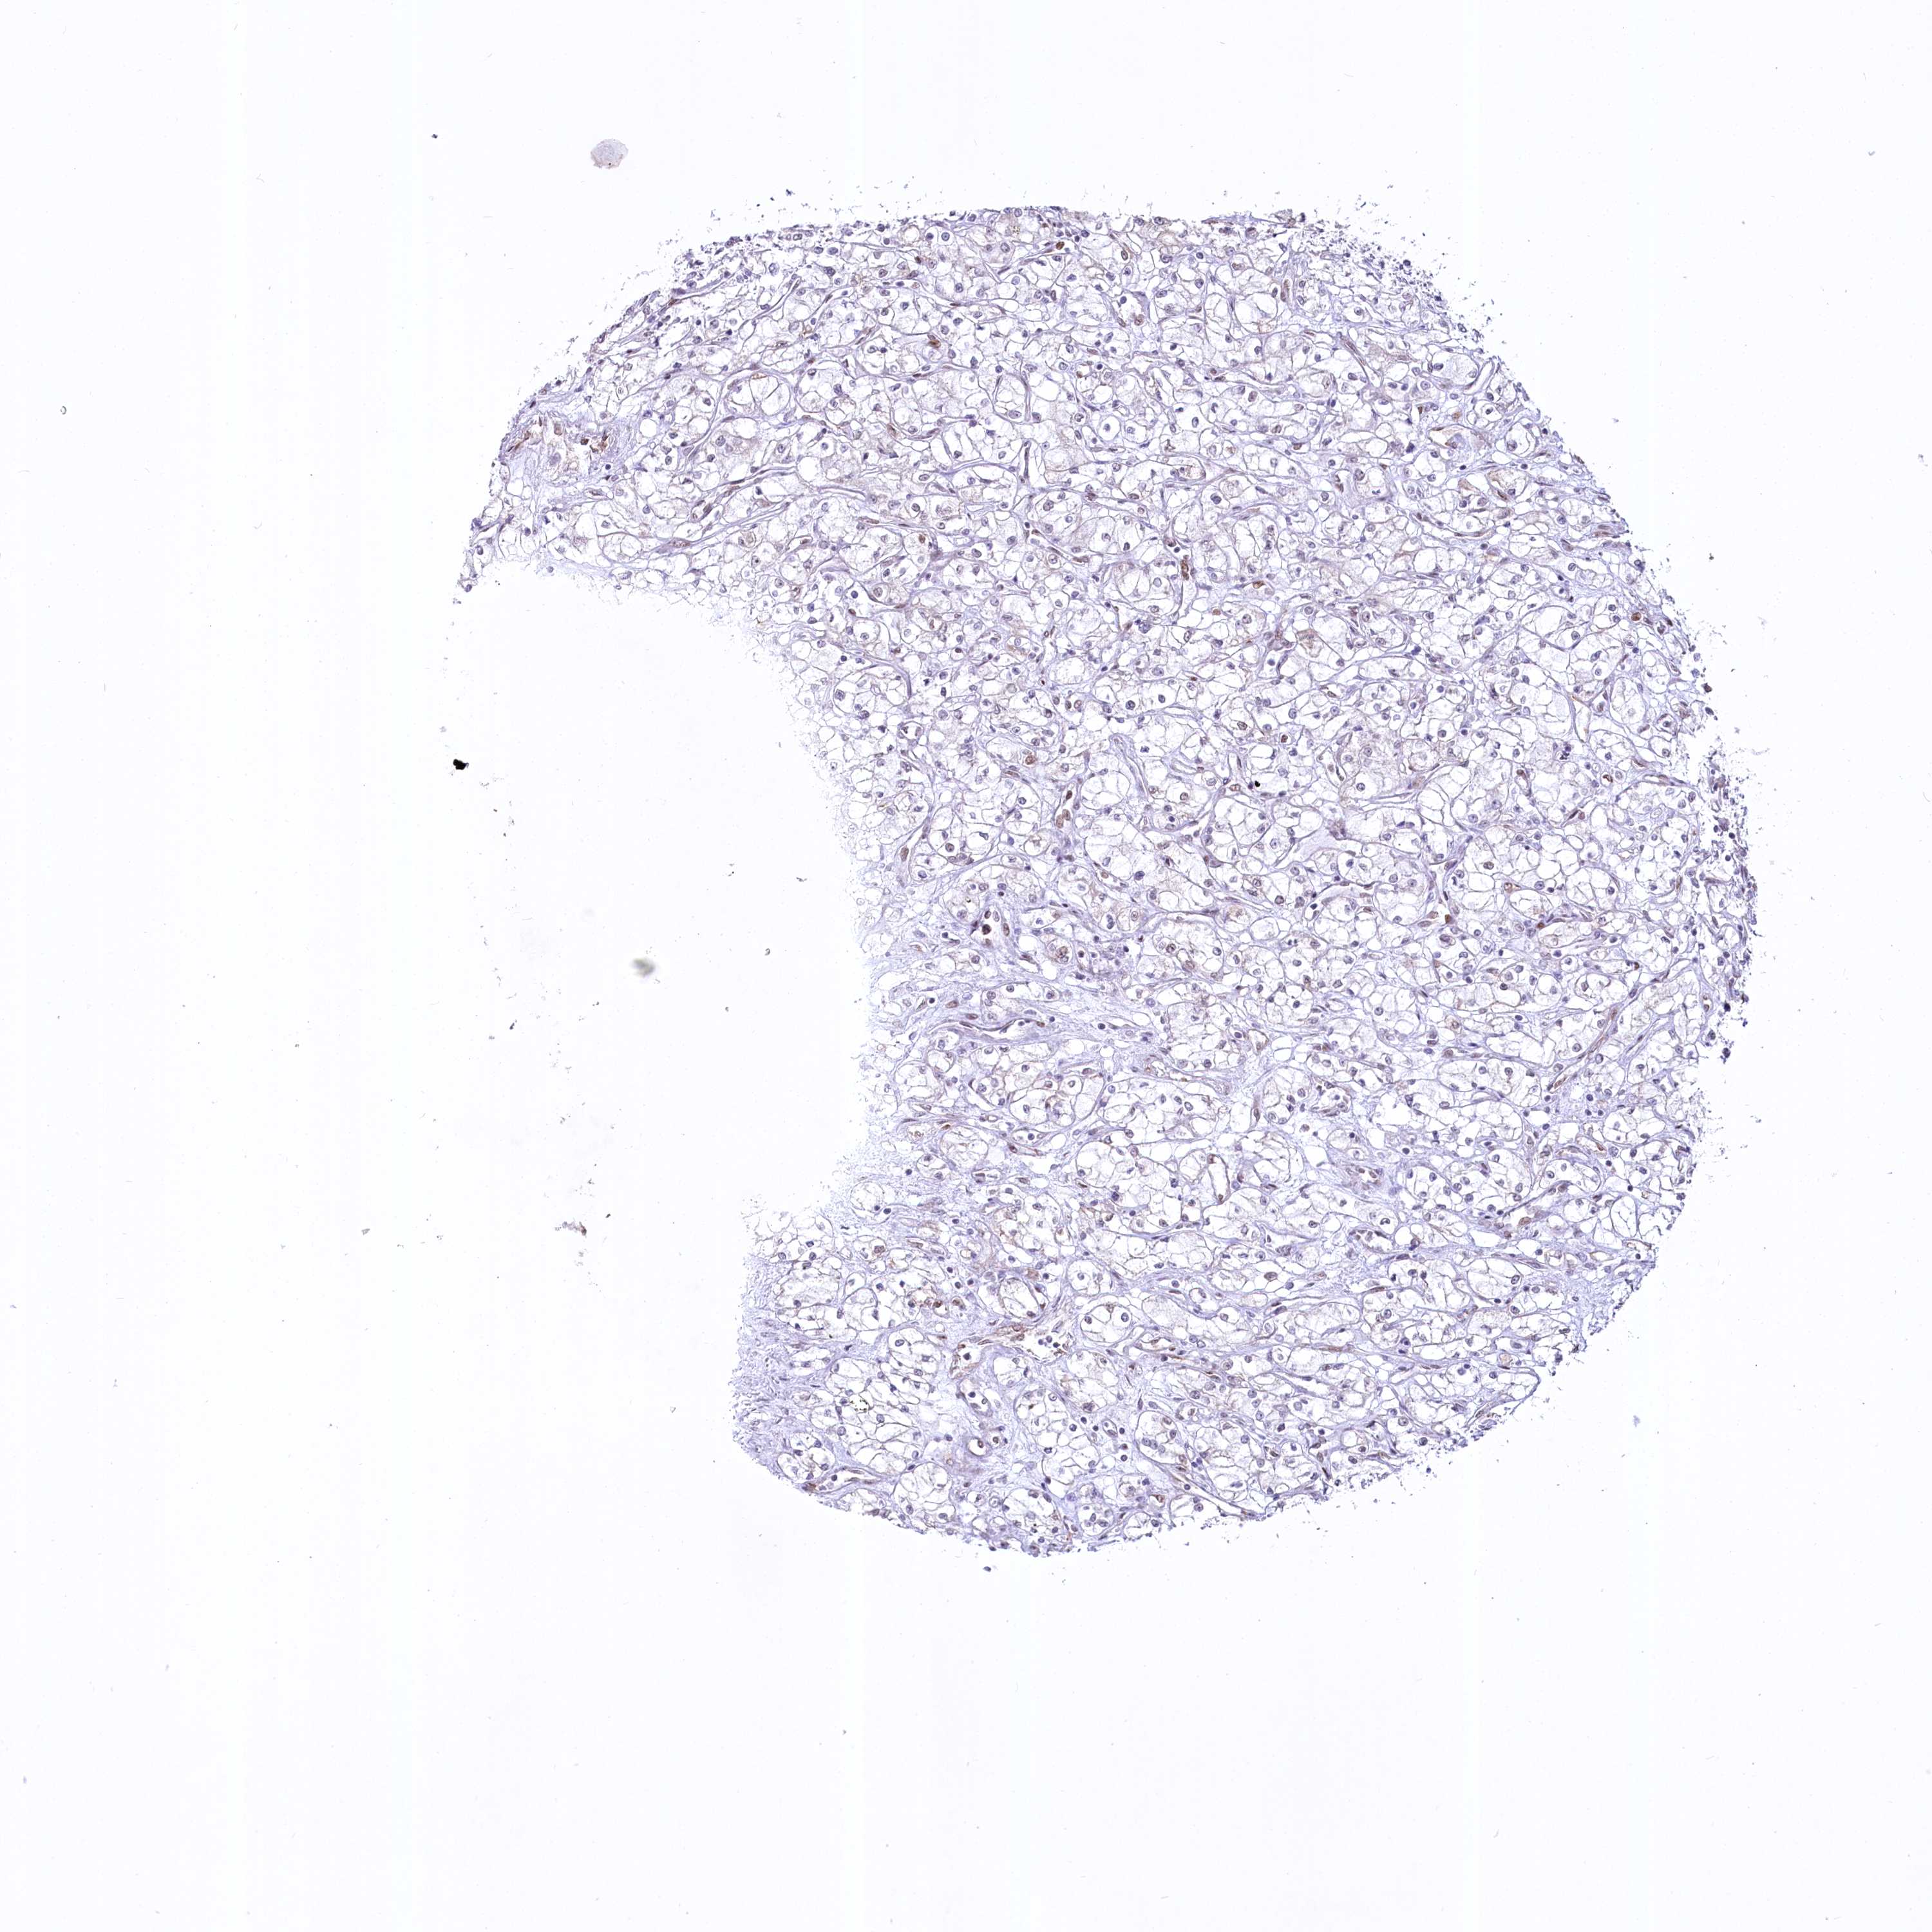

KIDNEY RENAL CLEAR CELL CARCINOMA (VALIDATION) - Interactive survival scatter ploti

The Survival Scatter plot shows the clinical status (i.e. dead or alive) for all individuals in the patient cohort, based on the same data that underlies the corresponding Kaplan-Meier plots. Patients that are alive at last time for follow-up are shown in blue and patients who have died during the study are shown in red.

The x-axis shows the expression levels (FPKM) of the investigated gene in the tumor tissue at the time of diagnosis. The y-axis shows the follow-up time after diagnosis (years). Both axes are complimented with kernel density curves demonstrating the data density over the axes. The top density plot shows the expression levels (FPKM) distribution among dead (red) and alive patients (blue). The right density plot shows the data density of the survived years of dead patients with high and low expression levels respectively, stratified using the cutoff indicated by the vertical dashed line through the Survival Scatter plot. This cutoff is automatically defined based on the FPKM cutoff that minimizes the p-score. The cutoff can be changed by dragging the vertical line or by entering a cutoff value in the square labeled "Current cut-off".

Under the Survival Scatter plot the p-score landscape (black curve; left axis) is shown together with dead median separation (red curve; right axis). Dead median separation is the difference in median mRNA expression between patients who have died with high and low expression, respectively. It is calculated as follows: median FPKM expression of dead patients with high expression - median FPKM expression of dead patients with low expression. This is intended to aid the user in visually exploring custom cutoffs and the associated p-scores and dead median separation.

Individual patient data is displayed and can be filtered by clicking on one or more of the category buttons on the top of the page. Categories describing expression level and patient information include: high, low, alive, dead, female, male and tumor stages. The scale of the x-axis can be toggled between linear and log-scale by clicking on the "x log" button. Mouse-over function shows TCGA ID, patient information and mRNA expression (FPKM) for each patient.

& Survival analysisi

Kaplan-Meier plots summarize results from analysis of correlation between mRNA expression level and patient survival. Patients were divided based on level of expression into one of the two groups "low" (under cut off) or "high" (over cut off). X-axis shows time for survival (years) and y-axis shows the probability of survival, where 1.0 corresponds to 100 percent.

YBX3 is not prognostic in Kidney Renal Clear Cell Carcinoma (validation)

Best expression cut offi

Based on the FPKM value of each gene, patients were classified into two groups and association between prognosis (survival) and gene expression (FPKM) was examined. The best expression cut-off refers the FPKM value that yields maximal difference with regard to survival between the two groups at the lowest log-rank P-value. Best expression cut-off was selected based on survival analysis .

When clicking on this number, the vertical dashed line indicating cut-off, the interactive survival plot, and the Kaplan-Meier curve will be adjusted to show results based on the best expression cut-off.

: 164.14

TCGA RNA samplesi

RNA-seq data is reported as average FPKM (number Fragments Per Kilobase of exon per Million reads), generated by the The Cancer Genome Atlas (TCGA) .

Normal distribution across the dataset is visualized with box plots, shown as median and 25th and 75th percentiles. Points are displayed as outliers if they are above or below 1.5 times the interquartile range. FPKM values of the individual samples are presented next to the box plot.

Average pTPM 241.3

Number of samples 100